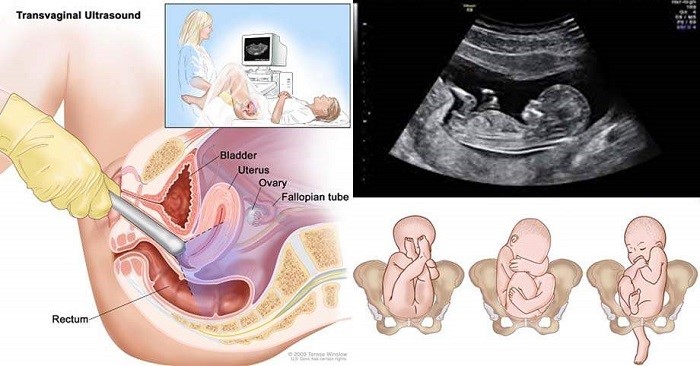

Như đã nói ở trên để theo dõi quá trình phát triển của thai nhi thì bác sĩ sẽ tiến hành 2 kĩ thuật, đó là siêu âm qua ngả âm đạo và siêu âm qua thành bụng.

Đối với siêu âm qua ngả âm đạo thì bác sĩ sẽ sử dụng một đầu dò thoa gel bôi trơn, co vào âm đạo và phát sóng âm để thu được hình ảnh hoàn chỉnh của bé. Phương pháp này rất an toàn, không gây ảnh hưởng cho sức khỏe hay bất kì đau đớn nào nhưng sẽ khiến bạn khá lúng túng. Tuy nhiên khi thai dưới 10 tuần tuổi, kích thước còn có bé nên buộc phải sử dụng phương pháp này mới nhìn thấy hình ảnh của bé qua màn hình.

Trong khi đó, khi bé đã trên 1 tuần tuổi thì có thể thay thế bằng phương pháp siêu âm qua thành bụng. Bác sĩ sẽ sử dụng dụng cụ siêu âm, bôi gel lên đó và sẽ rà khắp mặt bụng, trên màn hình sẽ hiện lên hình ảnh của thai nhi. Phương pháp này đã có mặt trên khắp các phòng khám, bệnh viện trên cả nước và được sử dụng thường xuyên trong y học.